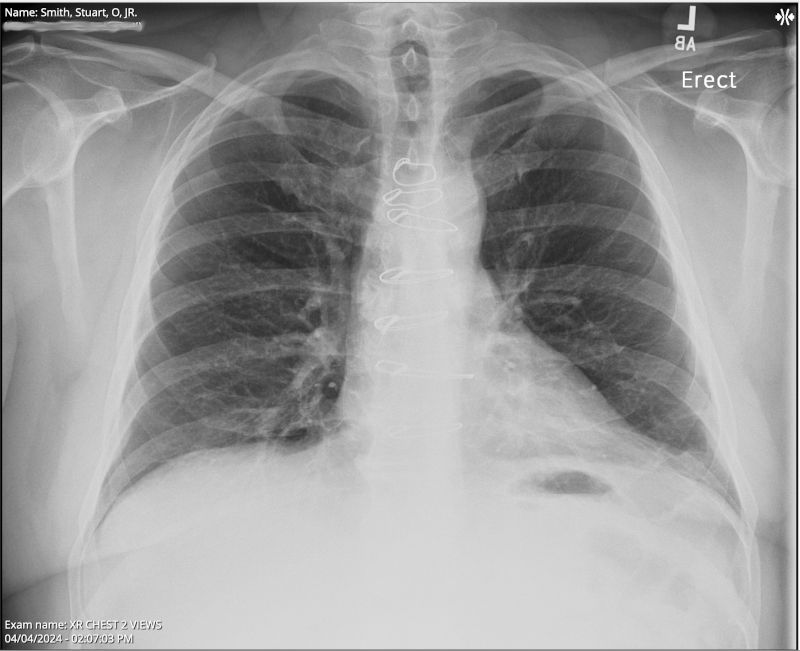

Chest X-ray

XR Chest 2 view Collected on April 5, 2024 7:42 PM . . . Impression 1. No evidence of acute cardiopulmonary process. . . . ORDERING CLINICIAN: EIRAN GORODESKI FINDINGS: Median sternotomy wires present. CARDIOMEDIASTINAL SILHOUETTE: Cardiomediastinal silhouette is normal in size and configuration. LUNGS: Lungs are clear. ABDOMEN: No remarkable upper abdominal findings. BONES: No acute osseous changes.

The results from my April 4, 2024, chest x-ray looked good. I still find it strange to view my x-rays and see some of the hardware that was left inside me after my April 27, 2023, septal myectomy (open-heart surgery) for Hypertrophic Cardiomyopathy. The notes above mention "Median sternotomy wires present," plus I also have retained epicardial pacing wires left inside me, which I have seen in other x-rays.

If you look very closely at the x-ray photo at the top of this blog post, and the following two x-ray photos, you can see the sternotomy wires: